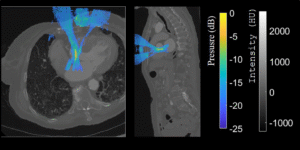

Our study in collaboration between Cardiawave and researchers from Physics for Medicine Paris presents a 3D numerical model of ultrasonic propagation through the ribcage, designed for applications in non-invasive cardiac ultrasound therapy.

Oct 21, 2025

Numerical modeling for cardiac ultrasound therapy: new paper in IEEE Transactions on Biomedical Engineering